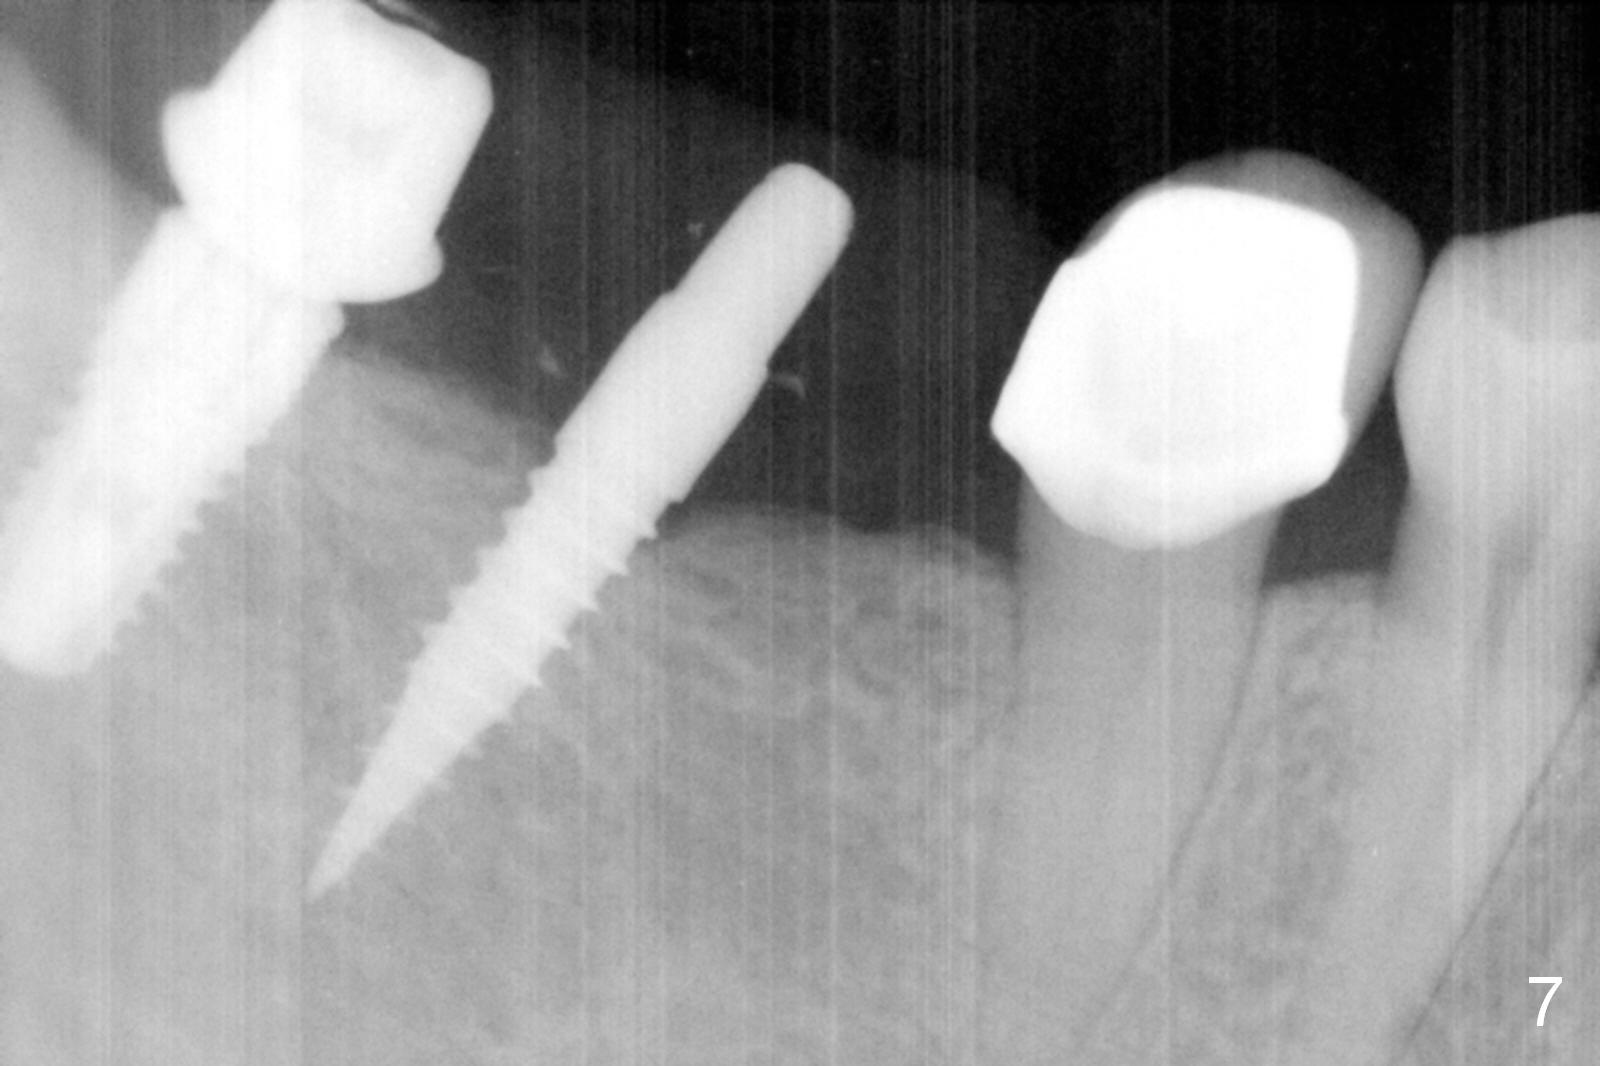

A preop photo shows different shape of pontics at #30 and 31 (Fig.1 <), suggesting different width of the edentulous ridge.  Two of 8 mm parallel pins are inserted for position and trajectory (Fig.2 (red dashed line: the superior border of the Inferior Alveolar Canal).  When they are removed from the osteotomy sites, the narrow ridge at #30 is shown (Fig.3).  A 3x12 mm 1-piece implant is placed at #30, while a 4.5x10 mm 2-piece one at #31 (Fig.4,5).  It appears that it is necessary to place an implant at #32, since the tooth #1 is present (Fig.5).  The suggestion is rejected by the patient due to finance.  After extraction of the tooth #32 and insertion of collagen plug, an immediate splinted provisional is fabricated to cover the #32 socket as well (Fig.6).  The provisional is modified (to remove the portion that covers #32 socket) 3-4 weeks postop.